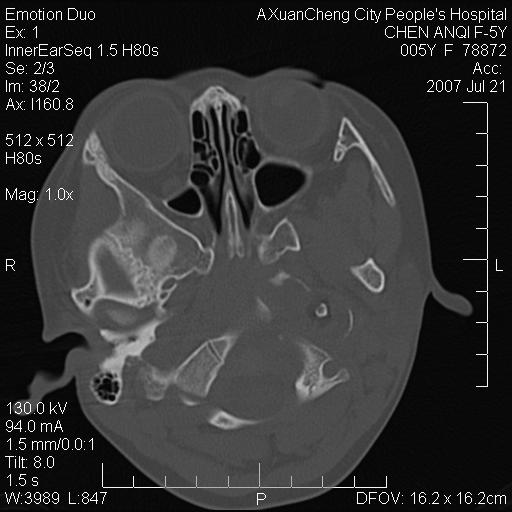

标题: PED0273:5岁,左耳流脓痛疼一周,颅底骨质破坏 [打印本页]

标题: PED0273:5岁,左耳流脓痛疼一周,颅底骨质破坏

患儿5岁,左耳流脓痛疼一周,左外耳道肉芽组织填塞 软组织窗显示病灶内结节状低密度影为气体密度

1.左耳中耳炎. 2.考虑伴颅内感染.

颅底骨质破坏,建议增强扫描

左侧中耳炎并胆脂瘤,左颞骨岩部骨质破坏并颅内感染积气。